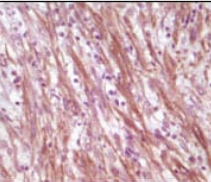

IHC    1/200 - 1/1000